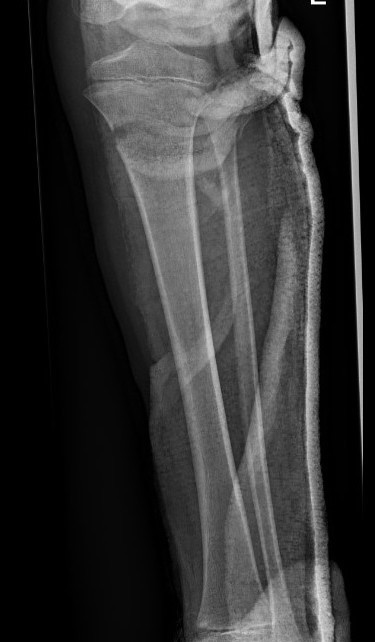

Manipulation and casting of malaligned Cozen fracture under anesthesia

Valgus malalignment